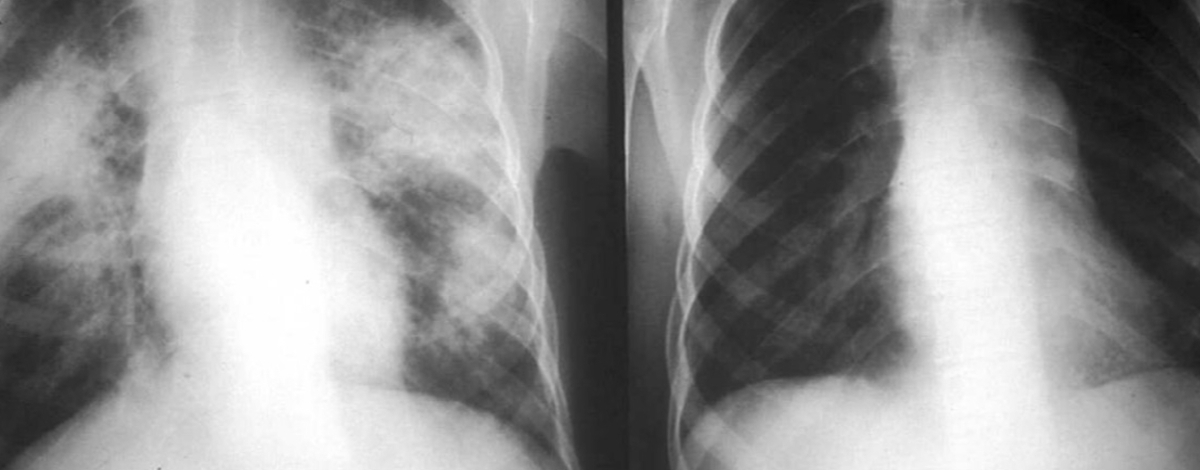

Malattia autoimmune dovuta a virus, germi o fattori ambientali, come la sarcoidosi.